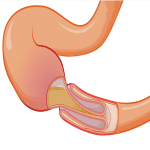

Lồng ruột (Intussusception) là một cấp cứu bụng ngoại khoa thường gặp, do một đoạn ruột lộn lại và chui vào lòng của đoạn ruột kế cận, là nguyên nhân của tắc ruột cơ học mà cơ chế vừa do bít vừa do thắt. Lồng ruột có thể gặp ở bất cứ lứa tuổi nào, nhưng thường gặp ở trẻ dưới 2 tuổi (chiếm tới 80% các trường hợp lồng ruột), trong đó gặp nhiều nhất là ở lứa tuổi 4 – 9 tháng. Lồng ruột gặp ở bé trai nhiều hơn bé gái từ 2 – 4 lần. Bệnh ít gặp ở trẻ suy dinh dưỡng, đa số gặp ở trẻ béo tốt, bụ bẫm…